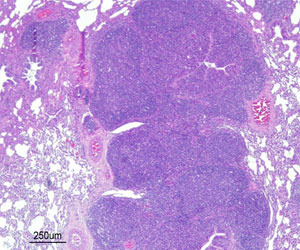

| Figure 1: Déplétion lymphocytaire sévère avec inflammation granulomateuse du tissu lymphoïde. Présence de corps d'inclusion intracytoplasmiques | Figure 2: Pneumonie broncho-intersticielle avec hyperplasie du tissu lymphoïde bronch-alvéolaire (BALT) causé par une infection expérimentale par Mhyo. |

Le Circovirus porcin de type 2 (PCV2) est l'un des agents pathogènes économiquement les plus importants de l'industrie porcine. Ce petit virus omniprésent est aujourd'hui reconnu comme l'agent essentiel de plusieurs maladies collectivement appelées maladies dues au circovirus porcin (PCVDs). Parmi ces PCVDs, la maladie systémique due au PCV2 (PCV-SD, auparavant connue comme le syndrome de l'amaigrissement post- sevrage, la MAP) est la plus significative. Bien que l'infection par le PCV2 soit nécessaire pour fournir le tableau complet des signes cliniques et les lésions de PCV-SD (figure 1), la maladie se reproduit plus efficacement avec la co-inoculation d'autres agents pathogènes. L'un de ces agents pathogènes est Mycoplasma hyopneumoniae (Mhyo). Mhyo est le principal agent étiologique de la pneumonie enzootique (PE), une maladie respiratoire chronique qui touche principalement les porcs en engraissement. Les lésions du type PE sont caractérisées par une pneumonie broncho-interstitielle avec hyperplasie du tissu lymphoïde broncho-alvéolaire (BALT) (figure 2). Avec d'autres agents pathogènes, y compris le PCV2, Mhyo a un rôle essentiel dans le complexe respiratoire porcin (CRDT). Par conséquent, le diagnostic et le contrôle de l'interaction entre les deux pathogènes est d'une importance capitale pour les éleveurs de porcs et les vétérinaires à travers le monde.